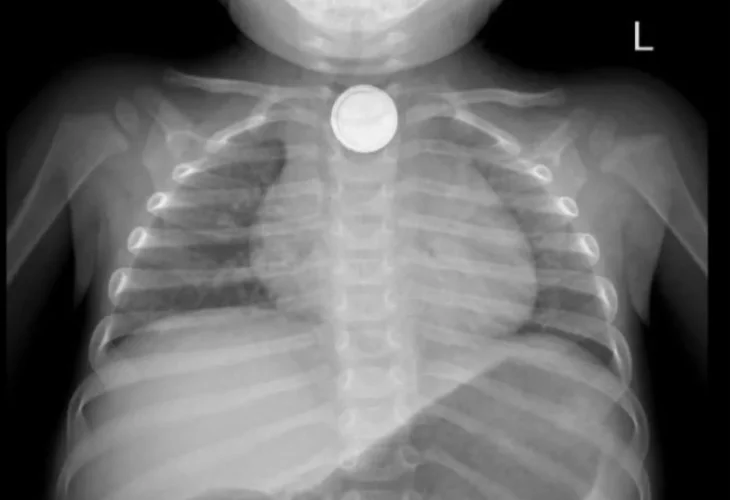

The X-ray that revealed the battery in the esophagus (Photo: Assuta Ashdod)Assuta Ashdod Medical Center reported today (Monday) that the life of a toddler who swallowed a lithium battery was saved this past week. The toddler, an 18-month-old from Ashdod, arrived at the hospital's pediatric ER after swallowing the lithium battery. Doctors noted: "This is an especially dangerous medical situation that can cause severe chemical and electrical burns in the digestive tract. It can lead to irreversible damage and even be life-threatening".

According to the hospital, upon arrival at the ER the toddler had difficulty swallowing and was drooling, and was classified as being in a life-threatening condition. Dr. Daniel Kahana, a pediatric resident, received the toddler in the pediatric ER and quickly recognized the severity of the situation. An X-ray identified the battery in the upper esophagus.